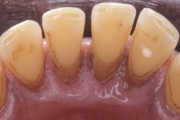

- igemepiir on taandunud (3)

- hamba kinnitussidemete kadu (3)

- igemealune hambakivi (4)